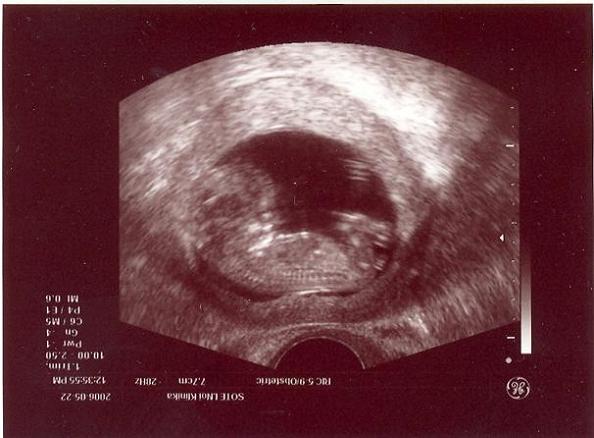

A 10. heti ijedség után szerencsére semmi komoly nem történt

, nagyon jól vagyunk. 20. heti UH-n minden rendben talált a doki, a hematóma eltűnt, a baba a korának teljesen megfelelő méretekkel rendelkezik (20+1-en voltunk, a gép a méretekre 20+2-öt írt). Viszont én nagyon renitens voltam, az APF-t nem csináltattam meg. Ennek több oka is van: 1. nagyon megbízhatatlannak tartom, 2. nekem Nátánnál és Hannánál is elkeveredett (más védőnői körzetbe ment, csak több hét után kaptam meg